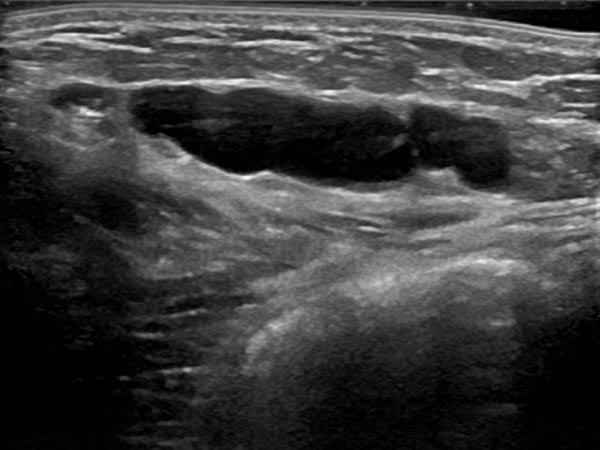

Circumscribed macrocystic malformation on the abdominal wall on ultrasound. Note the anechoic fluid in the thin-walled cystic spaces filled with liquid (lymph).